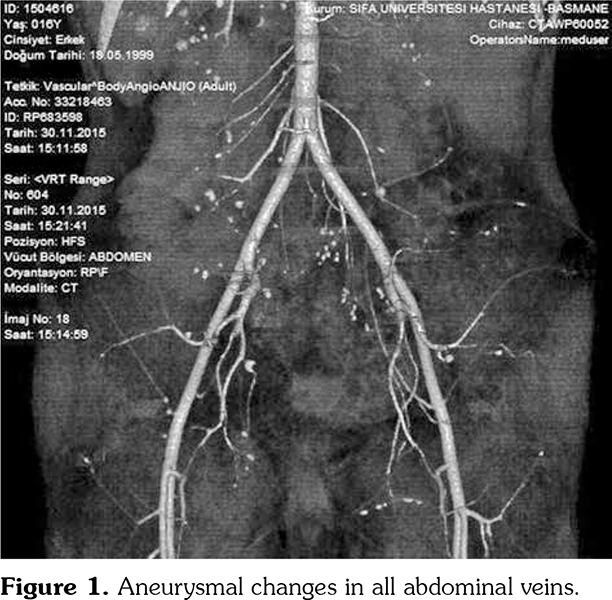

A 17-year-old male patient presented to the emergency department for evaluation of severe abdominal pain of approximately two months duration. His past history revealed that an abdominopelvic ultrasonography and a computed tomography angiography were performed before he was referred. They showed aneurysmal changes in all abdominal veins (Figure 1). Physical examination was notable for a blood pressure of 200/100 mmHg, paleness, myalgia in the legs and arms, and abdominal sensitivity. His weight and height were 28 kg (-3.7 standard deviation [SD]) and 149 cm (-3.89 SD), respectively. Laboratory evaluation revealed anemia (hemoglobin 9.6 g/dL, mean corpuscular volume: 64.3 fL) and elevated acute phase reactants (erythrocyte sedimentation rate: 82 mm/hour, C-reactive protein: 205.2 mg/dL). Urinary analysis showed +3 proteinuria. Complement components (C3, C4), antistreptolysin O, viral serologies, perinuclear antineutrophil cytoplasmic antibodies, and antineutrophil cytoplasmic antibody were observed as negative. The patient was accepted as PAN due to the imaging results, weight loss, myalgia, and renal involvement. For blood pressure elevation; sodium nitroprusside infusion was applied at first and then calcium channel blocker and angiotensin-converting-enzyme inhibitor were administered. During follow-up, he had a suspect seizure attack and complained of temporary loss of vision. A written informed consent was obtained from the patient.